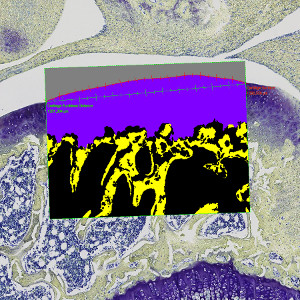

Figure 1

Coronal histological section of guinea pig knee joint, stained with Toluidine blue and Safron. Analysis box placed at tibia cartilage.